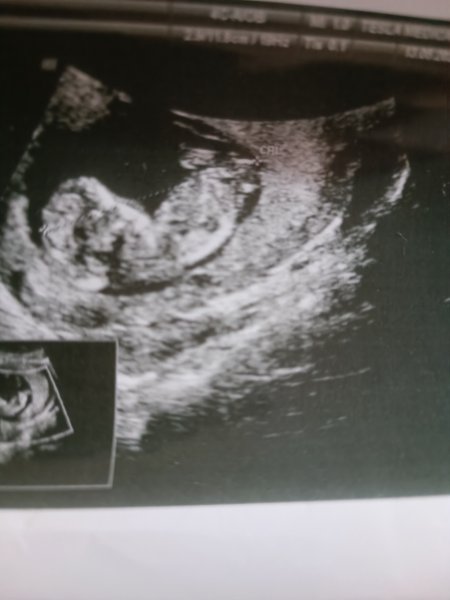

Canım. Benim bebiseme de bakar mısın 12+1Selamlar, Ultrason sonucuna göre cinsiyet tahmini var tabiki NUB TEORİSİNE GÖRE CİNSİYET başlıklı konumuzdan resimleri nasıl atacağınız ifade edilmiştir. Hemen konuda aşağıda yer alan özellikle cinsiyet belirlemede olması gereken çıkıntıların çıktısının olması gerekiyor. Bu resimlerin büyüğü var ise gönderin bize ya da linkini verdiğimiz konuya bakarak kendiniz de tahminde bulunabilirsiniz.

Vallahi ben uzman değilim ve Gaybı geleceği olacağı ancak Allah bilir ha illa yüzde verin diyor iseniz %52 kız diyelim![]()